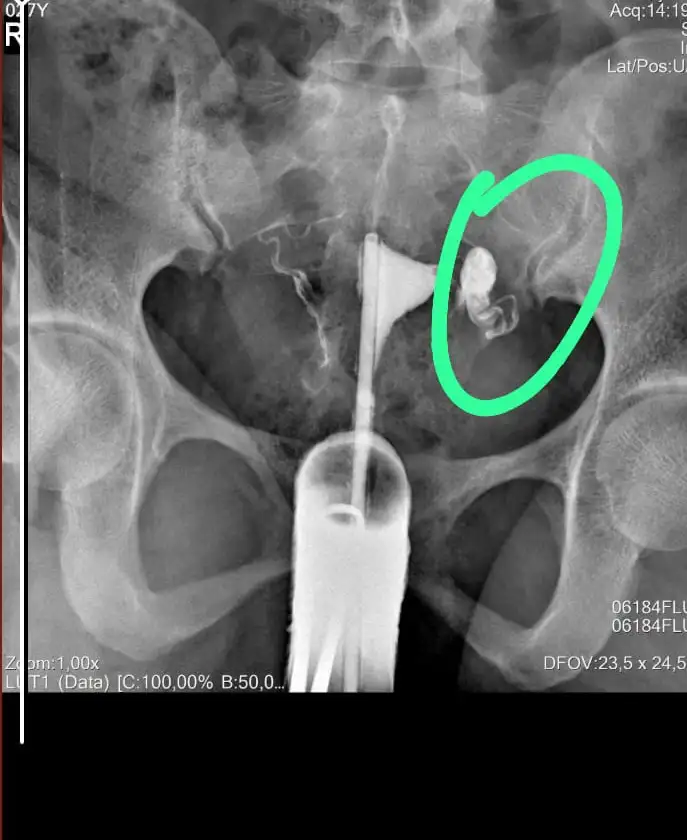

Kızlar merhaba mayısta genetik testi yaptırmıştım ve rahim filmi çekildim dün doktora gittim rahim filminde sol tüpümde Hidrosalpenks olduğunu söyledi ameliyat olmamı söyledi ve pıhtılaşma varmış. 2021 de doğal yollarla hamile kalmıştım ama ikiside düşükle sonuçlandı geçen sene ağustosda aşılama yaptırmıştım 10 gün sonra adetim geldi tutmamıştı adetimin üstünden 10 gün sonra lekem geldi ve test yaptığımda pozitif çıkmıştı doktorum progeston vermişti onu kullandım 1 hafta ama değerlerim yükselmemişti ilaçı bıraktım o zamandır hamile kalamadım dün doktor Hidrosalpenks olduğunu söyleyince ağlamaktan gözlerim şişmişti bugün tekrar gidecem ama üniversitye gidecem aşılama yaptırdığım doktora o da aynısı söylerse ameliyat olacam. Allah yardımcımız olsun inşallah sağlıklı evlatlarımız olur